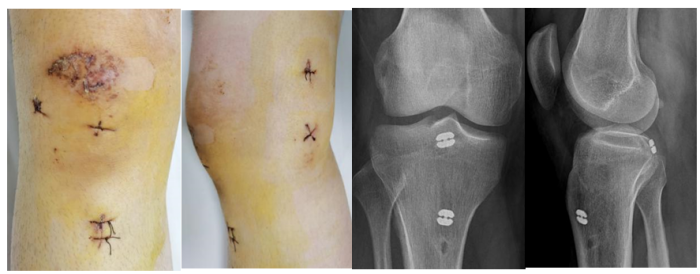

关节镜下微创手术切口及术后X线

经评估,余敏团队为这两位患者实施了关节镜下微创手术,通过在膝关节周围做2个小切口,将关节镜插入关节腔内,医生可以清晰地观察到关节内的情况以进行精准的骨折块复位,并使用特殊的器械固定。这类手术创伤小、恢复快,而且不需二次手术取出内固定物,术后患者没有明显的疼痛,膝关节功能恢复理想,患者感受很好。